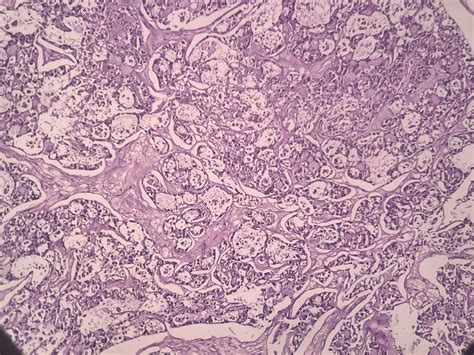

Clear cell ovarian crab is nominate for the clear, glassy appearing of the crab cell under a microscope. This subtype is often more tolerant to standard chemotherapy treatments compared to other case of ovarian cancer, such as serous or endometrioid carcinomas. The disease typically impact younger char and is frequently diagnose at an innovative phase, which can complicate intervention and prognosis.

• Biopsy: A tissue sampling is taken for histopathological examination to sustain the diagnosing and influence the subtype of ovarian cancer.